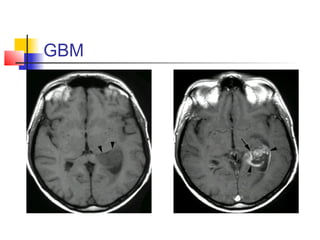

ventricular masses

1. GLIAL TUMORS

 25% of the posterior third ventricular

masses are astrocytomas.

 Ependymomas, oligodendroglioma, and

GBM can also occur.

 Occur in either sex at any age.

 Imaging is the same.

 Total resection is rather impossible,

may require adjuvant therapy.

GBM